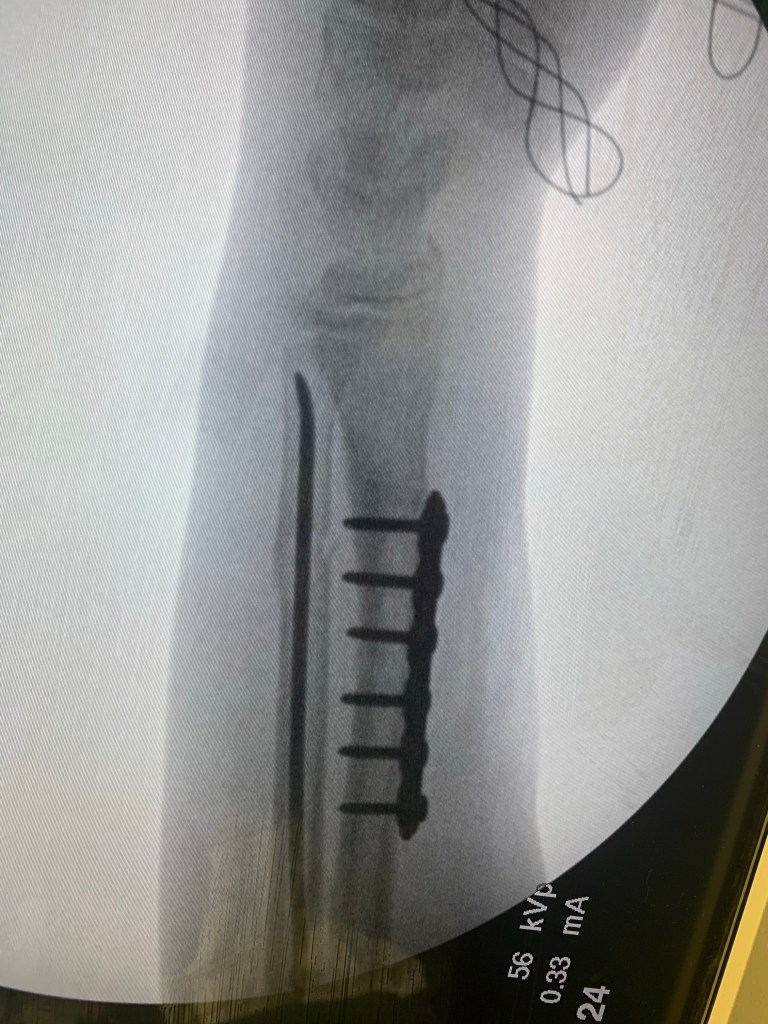

It is eerie to be the only person in a very large surgical waiting room. The only reason I am even allowed here is because the person I am waiting for is my 12 year old son. He has broken the same arm twice this year and is having surgery to place metal pins, to promote stability and healing.

Of course you worry about complications. What did they find in there? Did something happen with anesthesia? Why did it take so much longer than expected? These are logical thoughts. My mind buzzed through these rapidly and landed on ‘what if his bones are made of marshmallows?’ I am not kidding. I spent more than a minute wondering about this.